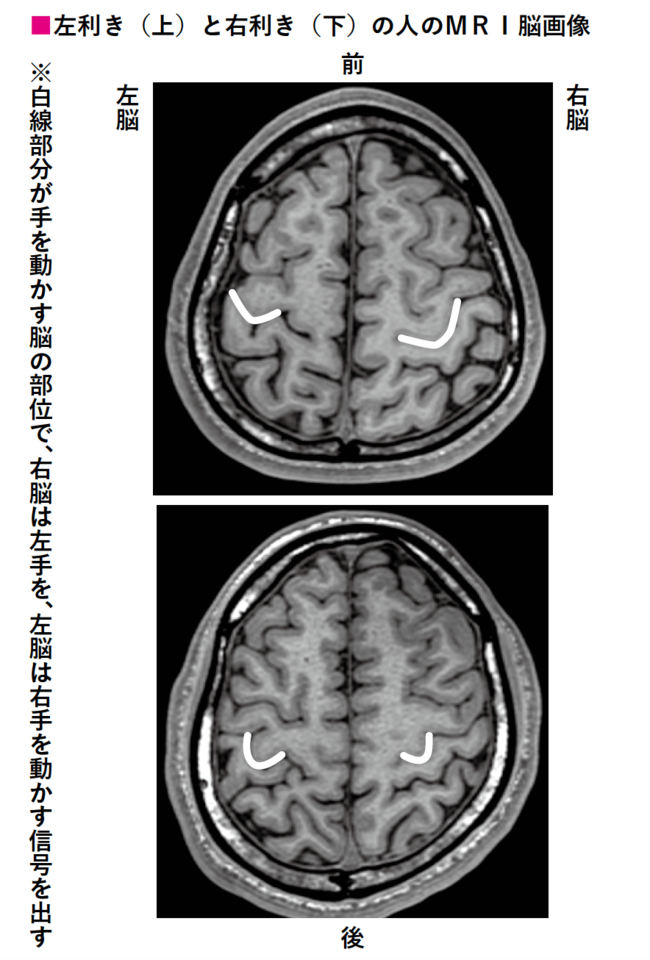

▼「利き手がどのように、いつ頃決まるのか。多くの脳を診断してきた、加藤プラチナクリニックの加藤俊徳医師に聞きました」

「加藤医師によると、0~2歳で決まります。0~2歳は両方の手を使いますが、だんだん無意識に使いやすい方の手を使う割合が増えてくるそうです。

個人差はありますが、平均的に2歳過ぎから見た目で違いが出てくるということです」